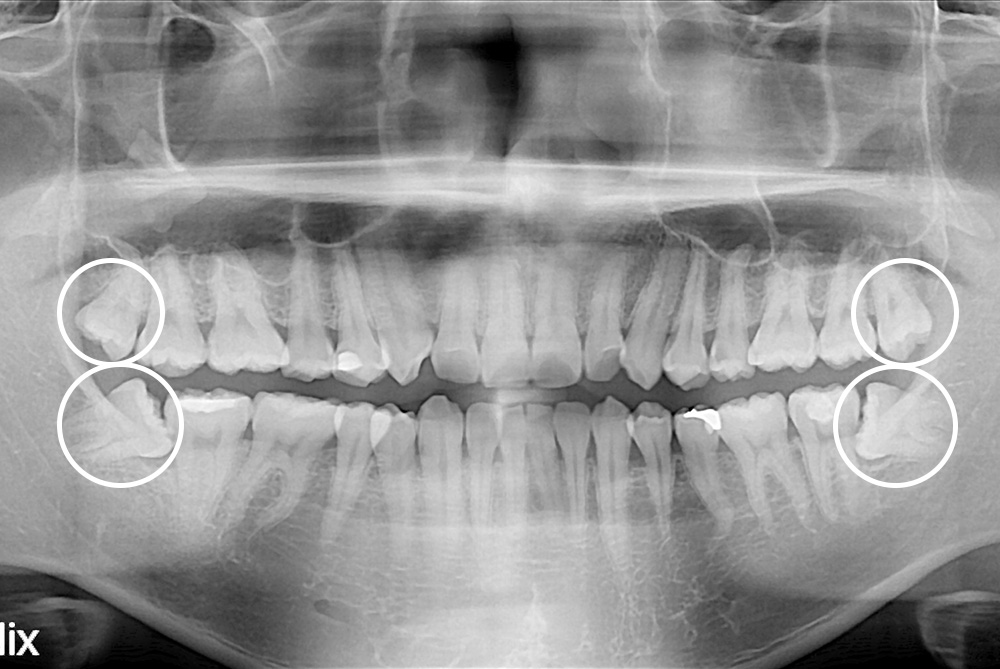

[사랑니] 매복 사랑니 발치

치료후 : 2017-09-29

세종치과는 구강악안면외과학 박사이신 원장님이 발치하는 치과입니다.